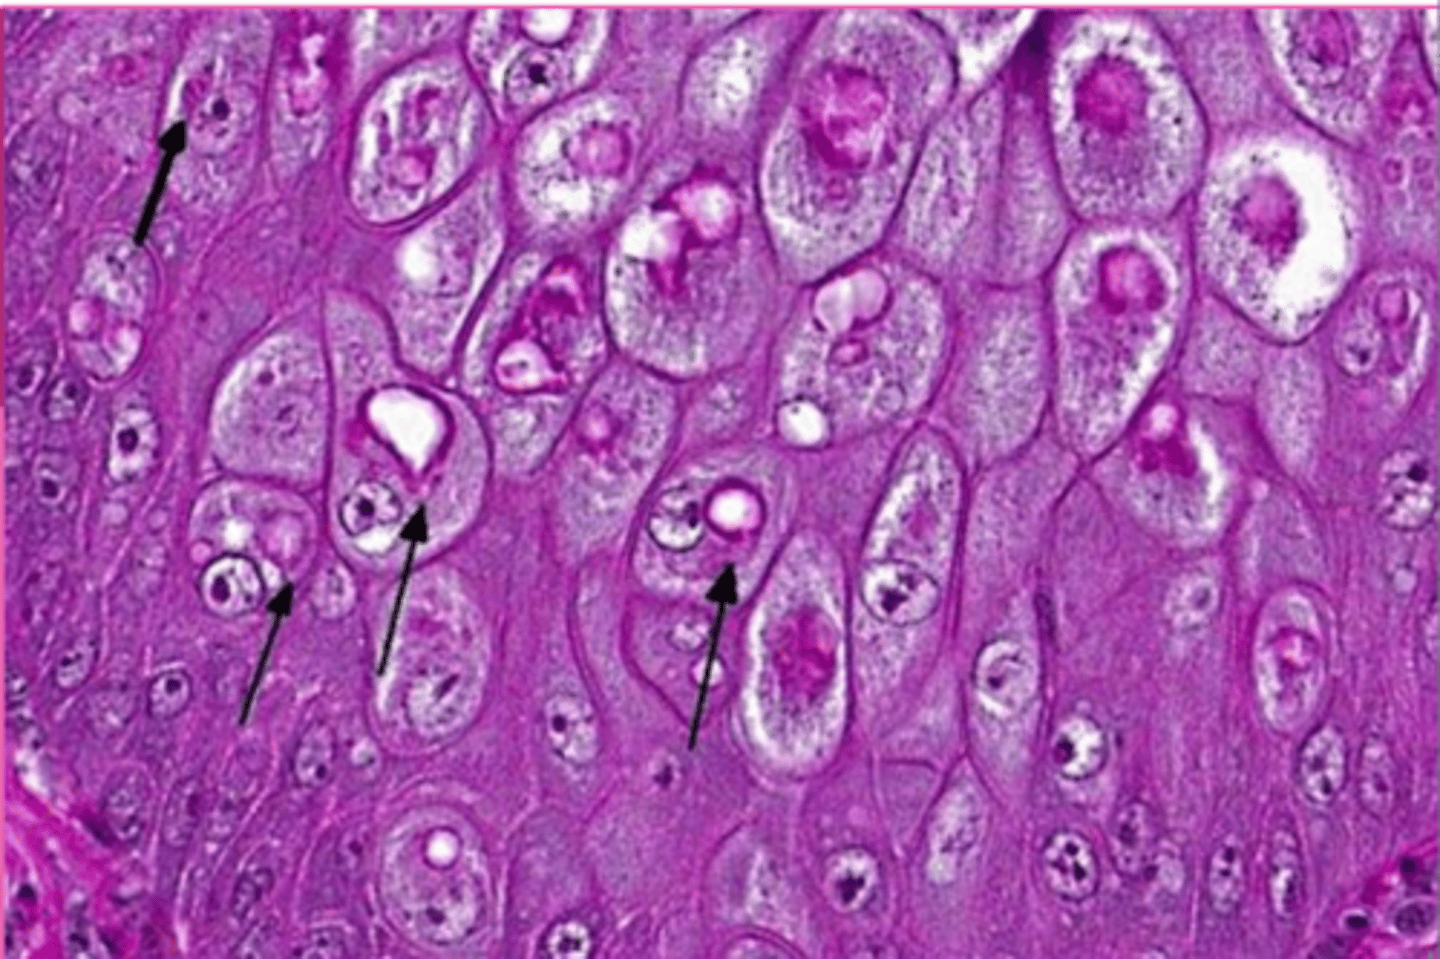

macrovesicular lipidosis

Which type of lipidosis is this describing?

Large, clear, sharply defined vacuoles that are larger than the nucleus, distend the

cytoplasm, and displace the nucleus to the periphery of the cell

macrovesicular hepatic lipidosis

yellow arrow?

microvesicular hepatic lipidosis

blue arrow?

displaced nucleus

blue arrow

macrocytic lipidosis - large cytoplasmic vacuole

yellow circle?